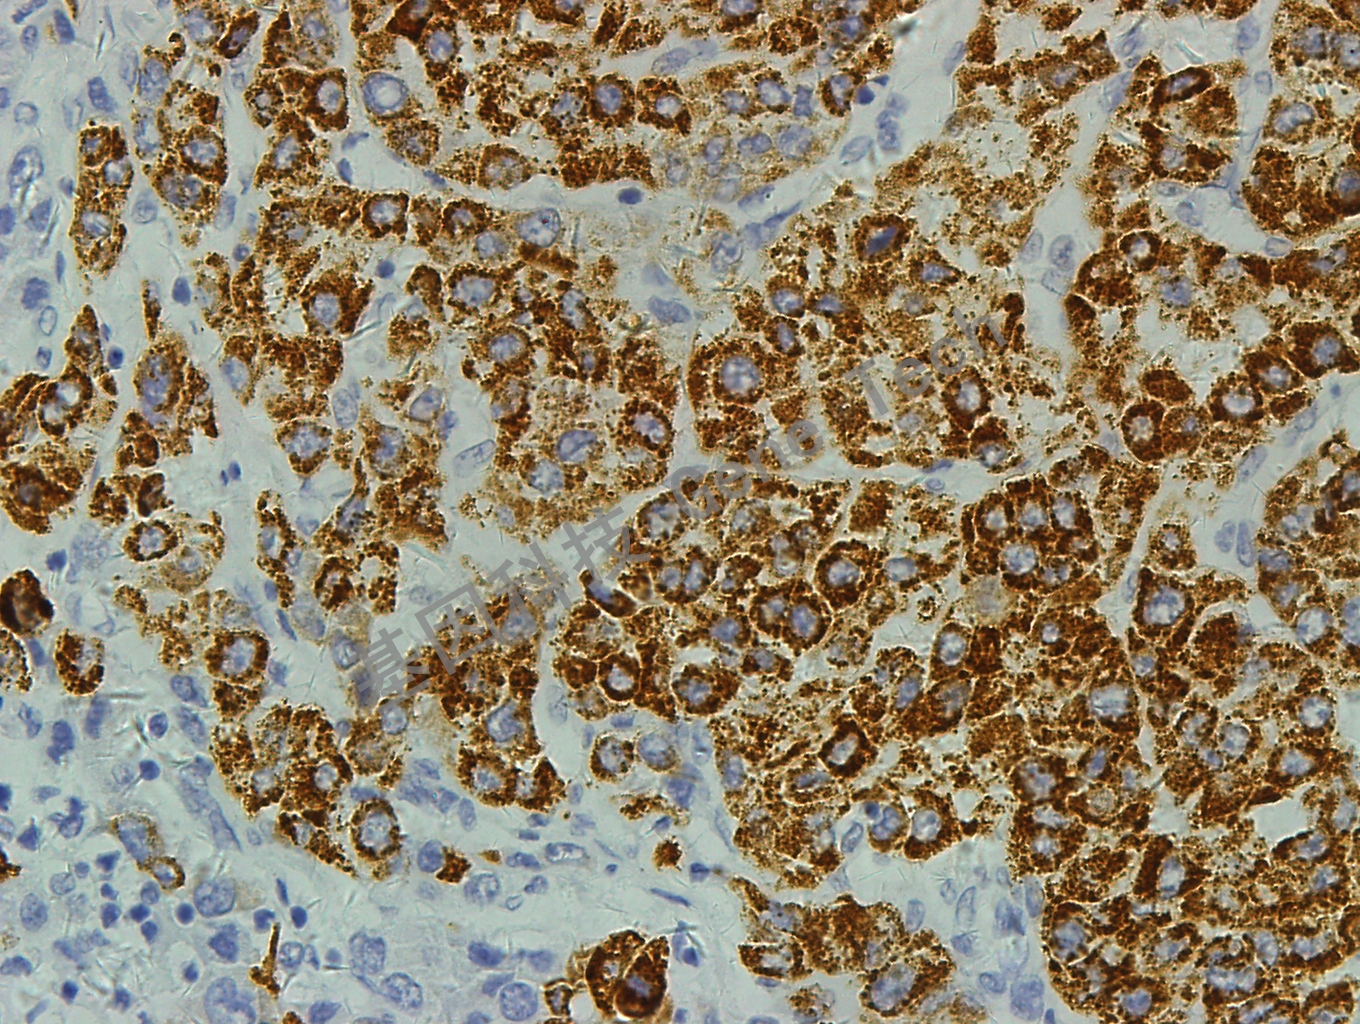

Hepatocyte又称Hep Par-1,是肝细胞的特异性标记物,识别肝细胞的线粒体。在肝脏中显示弥漫性的细胞质染色,伴有特性的颗粒状染色。可联合Arginase-1和Glypican-3用于原发性肝细胞癌与转移性肿瘤及胆管癌的鉴别诊断。

肝癌石蜡切片,用 Hep Par-1(GM7158)染色,细胞浆阳性,DAB 显色。